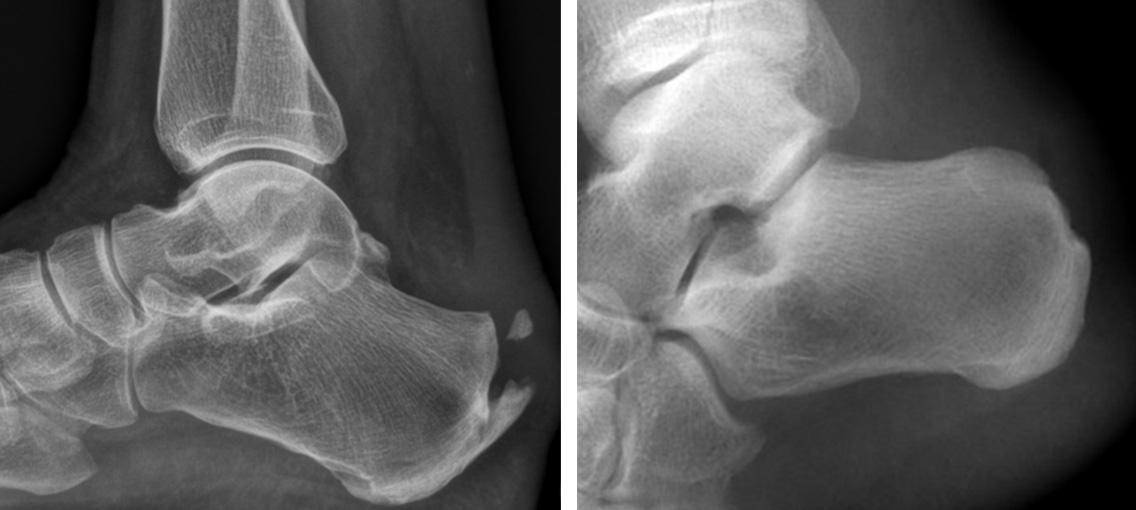

Diagnose

Ein Fersensporn zeigt sich als kleine, spitze Verhärtung am Ansatz der Achillessehne. Auf einem Röntgenbild sind die knöchernen Veränderungen gut zu erkennen. Zur Beurteilung der Vernarbung und Entzündung ist womöglich eine Magnetresonanztomographie (MRT bzw. engl. MRI für magnetic resonance imaging) oder eine Ultraschalluntersuchung erforderlich.

Bei Entzündungen am Ansatz der Achillessehne mit dorsalem Fersensporn ist die konservative Therapie etwas weniger zuverlässig. Hier wird bei bis zu zwei Drittel der Fälle ein operatives Vorgehen notwendig *. Dabei muss ein Teil der Achillessehne vom Fersensporn gelöst werden, um ihn abzutragen. Der geschädigte Teil der Achillessehne wird entfernt. Eine allenfalls vorliegende Haglund-Deformität kann gleichzeitig ebenfalls entfernt werden.

Bild: Universitätsklinik Balgrist